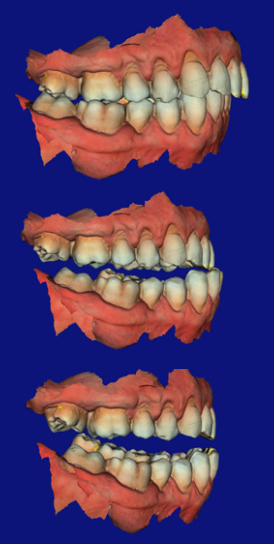

Clinical evaluation found a moderate Class II skeletal relationship with a retrognathic mandible. The lack of space for the tongue was contributing to airway collapse during sleep. Assessment followed British Society of Dental Sleep Medicine guidelines, including checks for sleep-related bruxism, dental erosion, and soft tissue indicators such as scalloped tongue.

Digital impressions were captured using an intraoral scanner with CS 3600 acquisition software. This was critical because mandibular advancement devices require multiple bite registrations at different protrusion levels — something that digital scanning handles far more accurately than traditional impressions.

The software's undercut tools helped identify where tooth anatomy could be modified — for example, using direct composite attachments to create undercuts that improve appliance retention. Overjet and overbite measurements were recorded at the initial scan for comparison at future reviews to monitor any unwanted tooth movement.

The full arch scans were exported to ResMed, where the 3D model was aligned with a virtual articulator and the Narval CC appliance designed using a completely digital workflow — no physical models, no alginate, no stone.